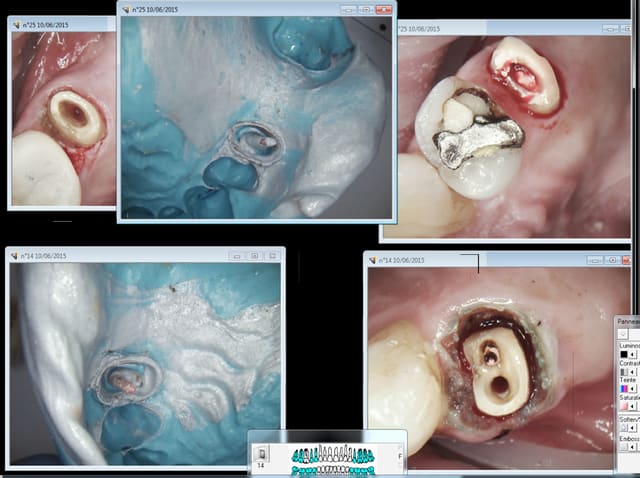

Alors RTE ou pas RTE ( meme patient) ? Pas trop mal cette endo, on est jamais à l'abri d'un coup de bol ! -))))

Chicot29 , tu utilises un bistouri electrique pour faire le méchoui de gencive ?

La prothèse c'est pas mon truc. Mais dans le temps imparti pour faire le tt de A à Z l'expérience montre qu'il faut en consacrer le plus pour l'endo. -))))